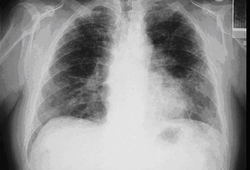

[Figure caption and citation for the preceding image starts]: Casos de pneumonia sem resoluçãoCriado no BMJ Knowledge Centre com base nas tabelas de Athanasia Pataka [Citation ends].